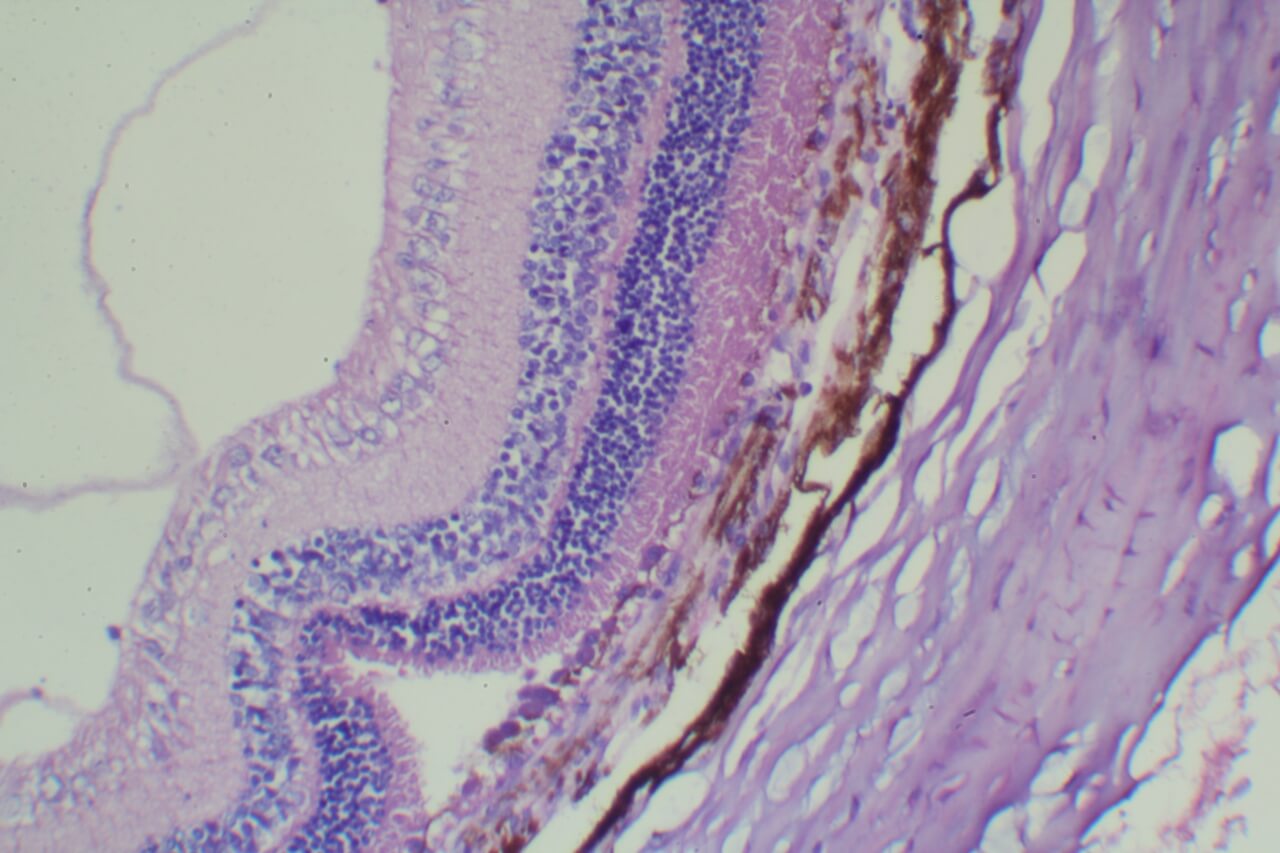

特殊染色